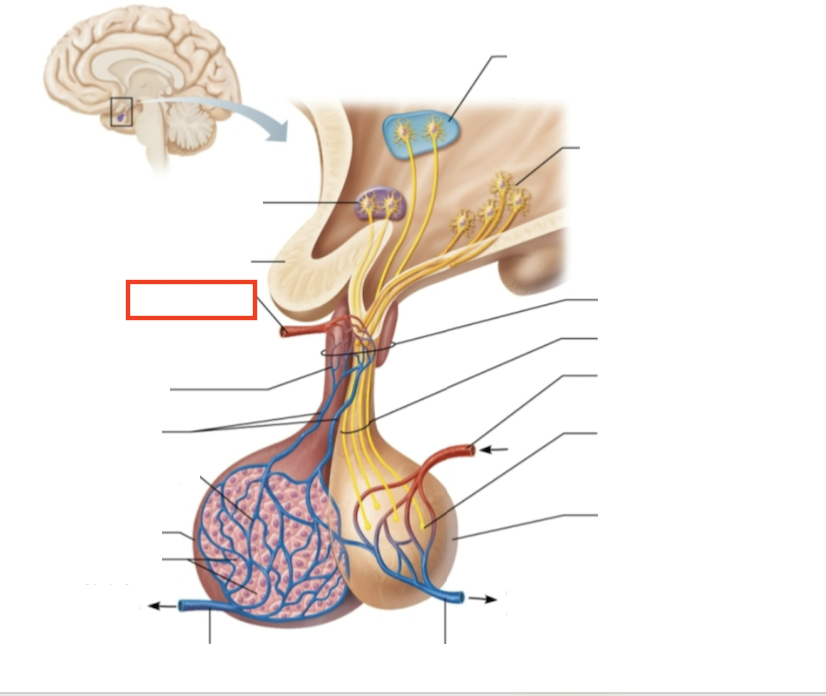

What structure is highlighted?

testes (male)

What structure is highlighted?

hypothalamic neurons in the paraventricular nuclei

What structure is highlighted?

neurons in the ventral hypothalamus

What structure is highlighted?

infundibulum (connecting stalk)

What structure is highlighted?

hypothalamic-hypophyseal tract

What structure is highlighted?

inferior hypophyseal artery

What structure is highlighted?

neurohypophysis (storage area for hypothalamic hormones)

What structure is highlighted?

posterior pituitary

What molecules are produced here?

oxytocin, ADH

What structure is highlighted?

venule

What structure is highlighted?

venule

What molecules are produced here?

TSH, FSH, LH, ACTH, GH, PRL

What structure is highlighted?

secretory cells of adenohypophysis

What structure is highlighted?

anterior pituitary

What structure is highlighted?

secondary capillary plexus

What structure is highlighted?

hypophyseal portal veins

What structure is highlighted?

primary capillary plexus

What structure is highlighted?

superior hypophyseal artery

What structure is highlighted?

superior hypophyseal artery

What structure is highlighted?

optic chiasma

What structure is highlighted?

hypothalamic neurons in the supraoptic nuclei